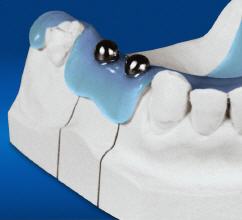

Die reale Knochenhöhe wird mit Hilfe einer Tiefziehschiene mit eingearbeiteten Metallkugeln ermittelt. Bei digitalen Röntgengeräten kann gegebenenfalls auf die Messaufnahmen verzichtet werden, da sie über ein integriertes Messtool verfügen. Zur Detailabklärung kann es erforderlich sein, zusätzliche Aufnahmen von einzelnen Zahnabschnitten zu machen.